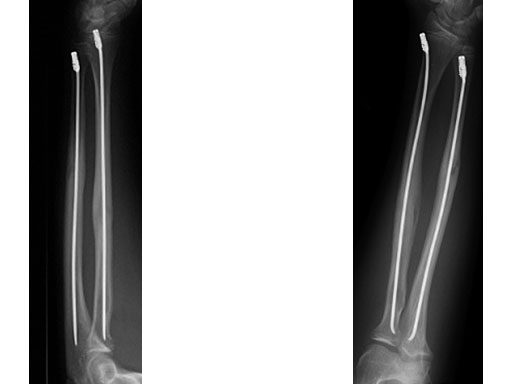

Case 1: Transverse forearm, shaft fracture (22D/4.1), 9-year-old girl.

Case provided by Theddy Slongo, Bern, Switzerland